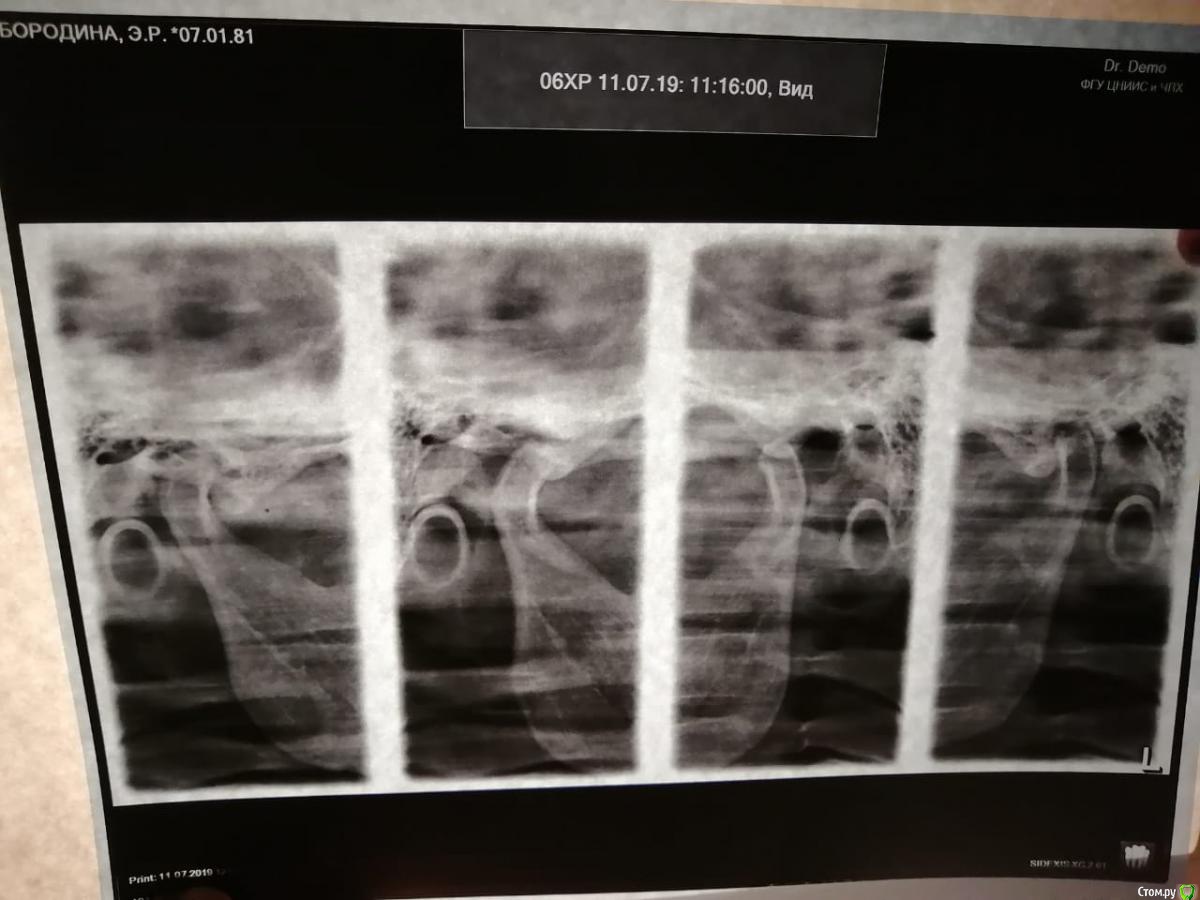

Эльза031008 Опубликовано 24 ноября, 2019 Поделиться Опубликовано 24 ноября, 2019 Добрый день уважаемые врачи . Помогите определиться с правильностью метода протезирования коронок на верхние передние зубы при мезиальном прикусе? Мне 38 лет, с рождения нижняя челюсть больше верхней, ордонтическое лечение не проходила , в верхнем ряду один зуб на штифте с 15 лет , сейчас встал вопрос о замене , штифт уже не заменить , при нескольких консультациях ортопеды не берутся ставить коронки или имплатант , или готовы сделать,но без гарантии, что конечно меня не устраивает. В итоге один ортопед предложил вариант протезирования после поднятия верхнего ряда , я согласилась на данный вариант. Сначала носила гибкую пластинку на ночь 2 месяца, а сейчас сделали пластмассовые временные коронки на весь верхний ряд , которые я должна носить не менее 6 месяцев , перед постановкой постоянных . Зубы не обтачивали, на них сверху прикрепили на весь ряд три готовые слитные коронки слева ,справа и спереди с подговленный гипс. модели , при этом верхний ряд вывели вперед за нижние путем утолщения коронок и на несколько мм выступ на нижние с помощью увеличения высоты . По прикусу мне не удобно в состоянии покоя, долго обтачивали чтобы подогнать коронки , но я чувствую что с прикусом все не так , жевательеые поверхности касаются только по внешнему краю внутри если проводить языком то есть пустоты , нижние передние садятся на верхние и я испытываю наибольшее давление именно на передние зубы, когда ем пища плохо пережевывается нижние передние зубы при этом проходяться по верхним с клацканьем. Когда уже все сделано я понимаю что методом ручной подгонки нельзя было делать... По ортодонтии несколько ортодонтов в том числе профессор Арсеньева сказала что поможет только операция , на операцию я не соглашусь , большие риски. Посоветуйте план возможного протезирования и где в Москве есть такие специалисты протезирующие с такой проблемой ?возможно ли предваоительное моделирование, чтобы более или менее подобрать коронки по прикусу и не вызвать дисфункцию суставов и было более менее комфортно? При этом текущие конструкции нужно снять? Ссылка на комментарий